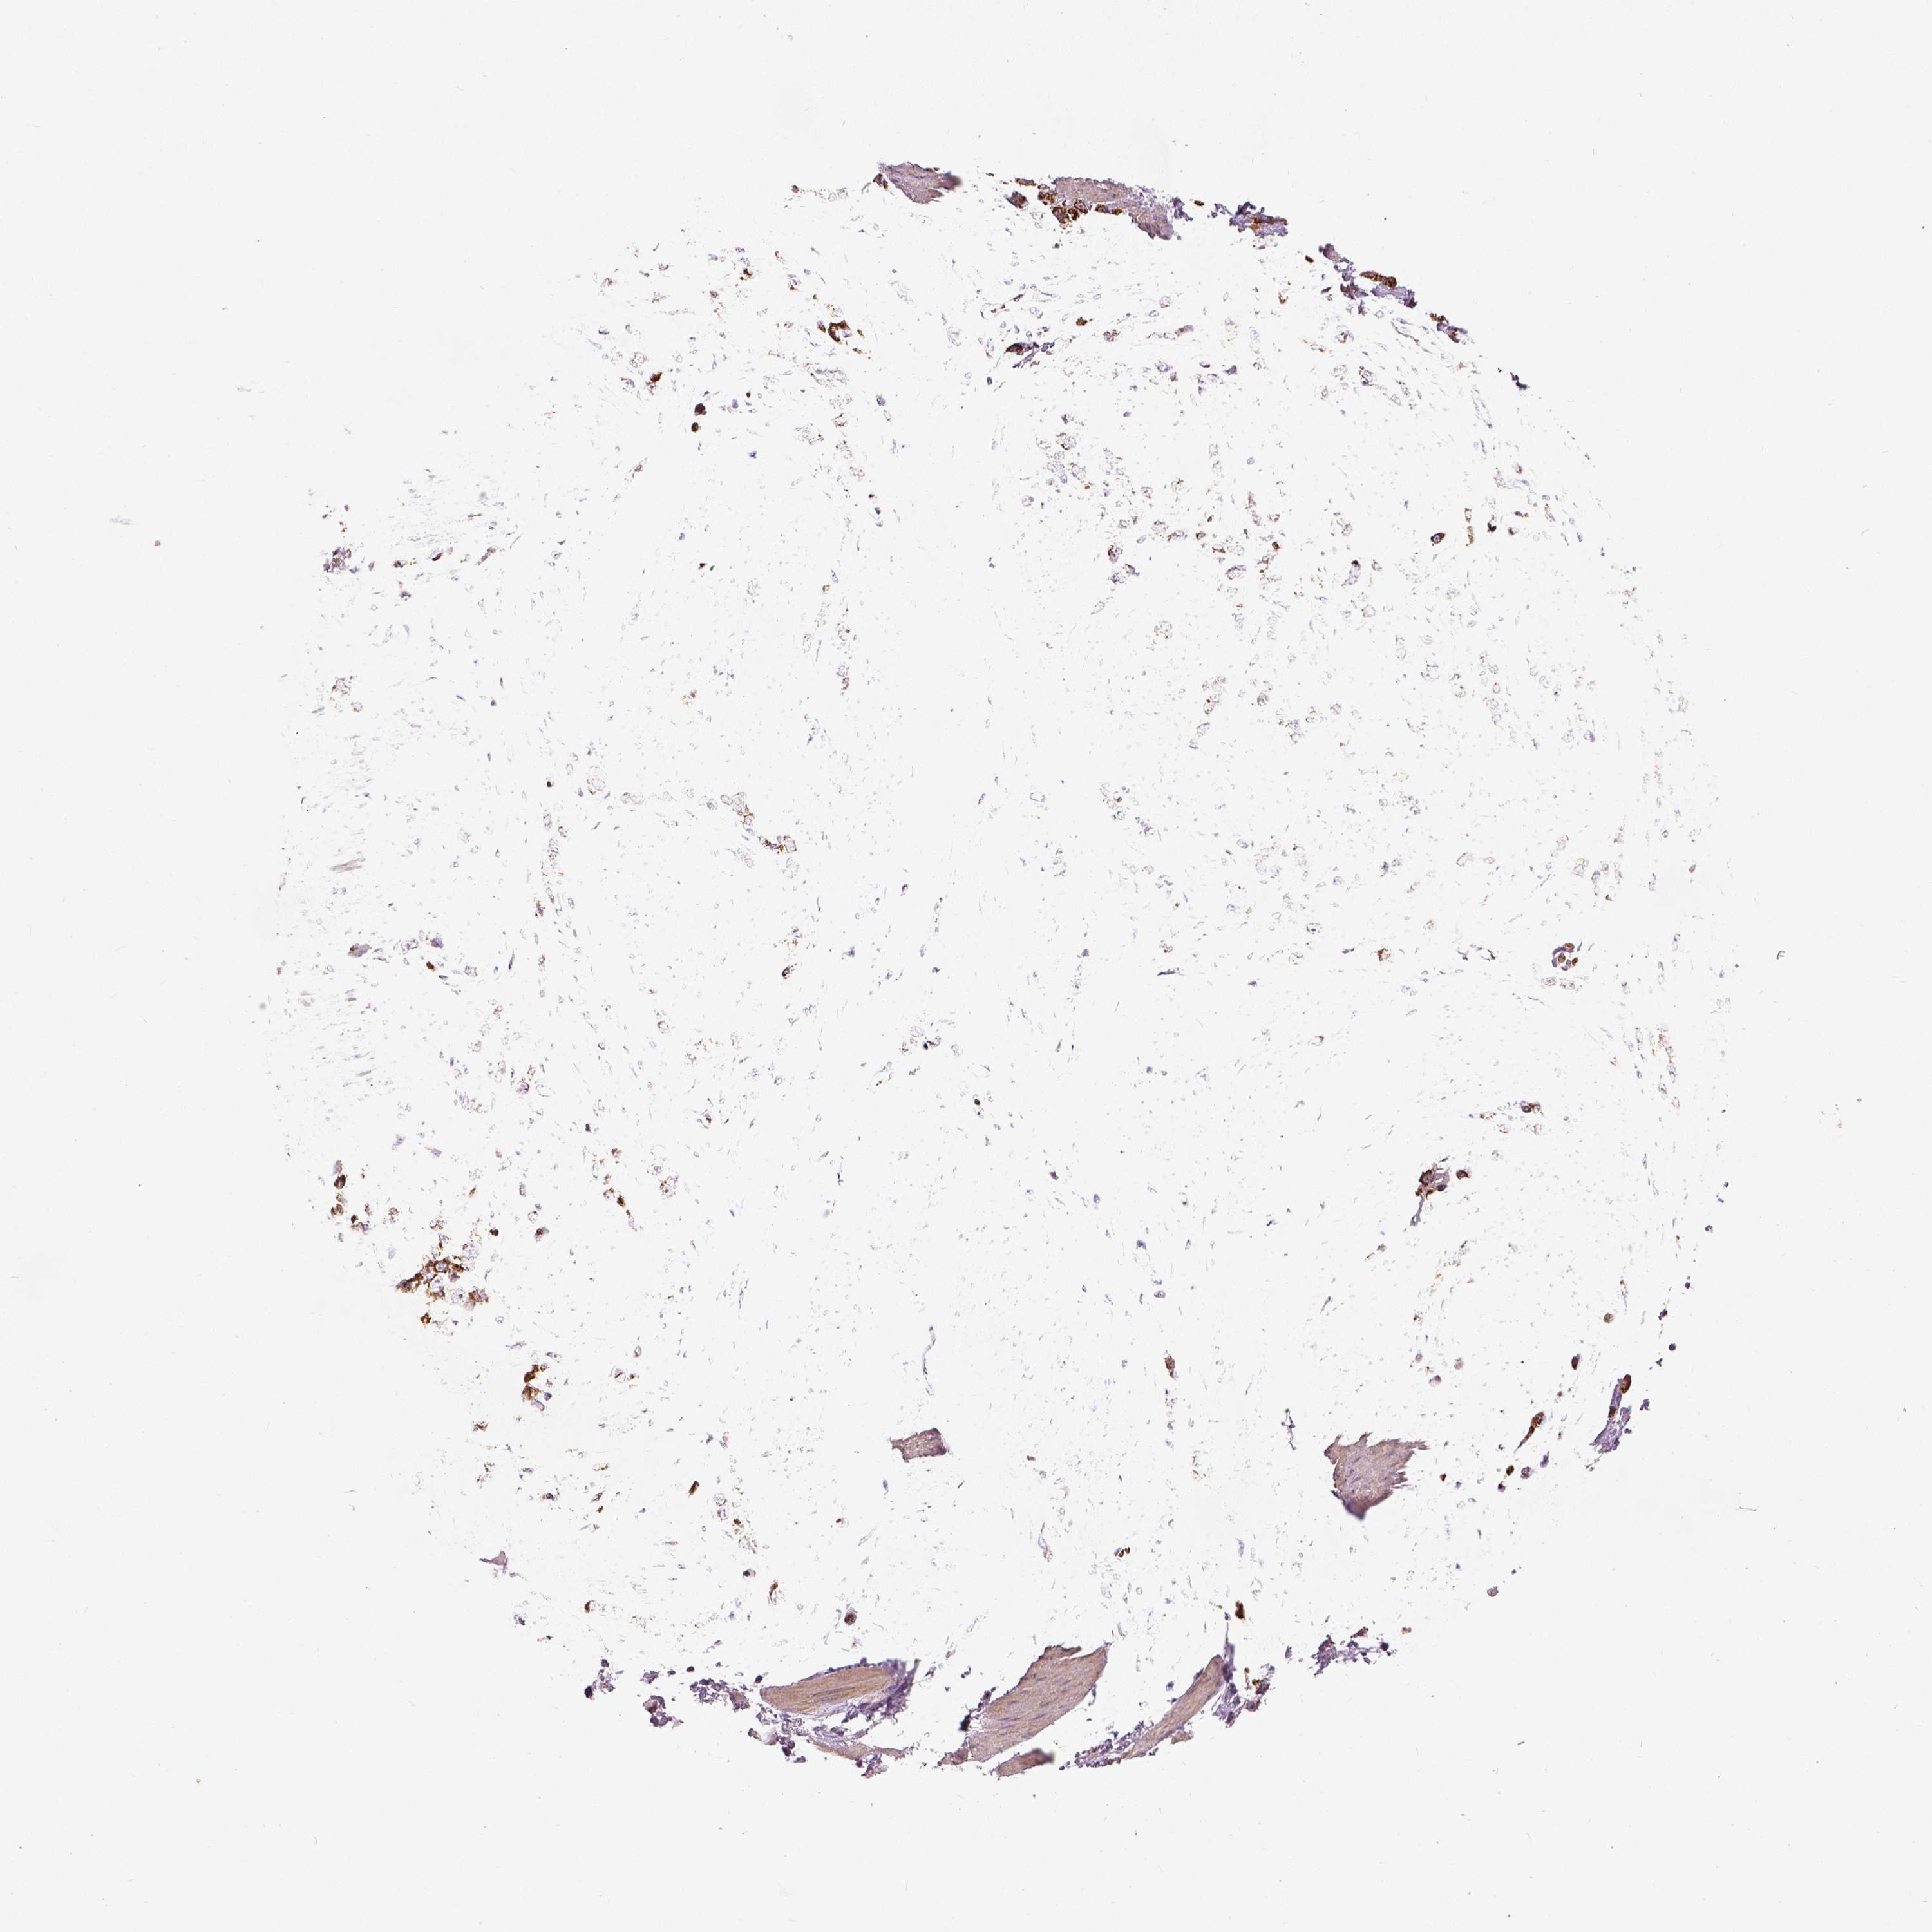

STOMACH CANCER - Protein expressioni

A mouse-over function shows sample information and annotation data. Click on an image to view it in a full screen mode. Samples can be filtered based on level of antibody staining by selecting one or several of the following categories: high, medium, low and not detected. The assay and annotation is described here.

Note that samples used for immunohistochemistry by the Human Protein Atlas do not correspond to samples in the TCGA dataset.

Antibody stainingi

Antibody staining in the annotated cell types in the current human tissue is reported as not detected, low, medium, or high, based on conventional immunohistochemistry profiling in selected tissues. This score is based on the combination of the staining intensity and fraction of stained cells.

Each image is clickable and will lead to virtual microscopy that enables deeper exploration of all samples and also displays staining intensity scores, fraction scores and subcellular localization as well as patient and tissue information for each sample.

Antibody HPA036978

Antibody HPA036979

Antibody CAB068215

Staining

High

Medium

Low

Not detected

Intensity

Strong

Moderate

Weak

Negative

Quantity

>75%

75%-25%

<25%

None

Location

Nuclear

Cytoplasmic/membranous

Cytoplasmic/membranous,nuclear

Adenocarcinoma, NOS